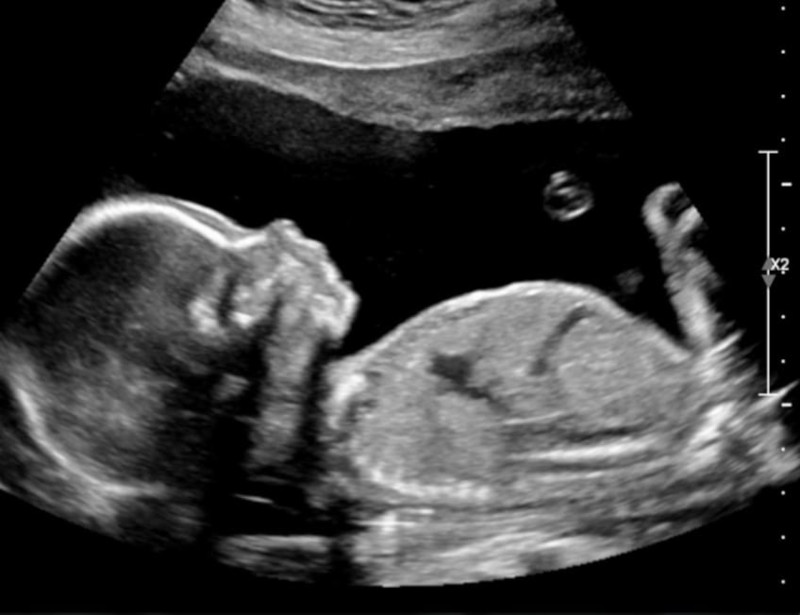

The 2D ultrasound image, often referred to as "black and white," provides a flat, two-dimensional view of the fetus, allowing healthcare providers to assess the baby's growth, check for any abnormalities, and monitor the overall health of the pregnancy. This type of imaging is typically used in the early stages of pregnancy and is essential for routine check-ups.